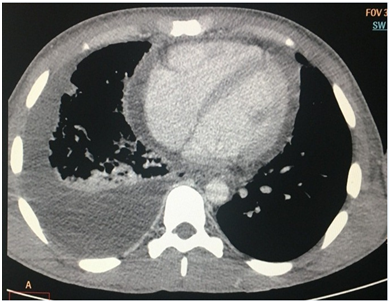

The initial thorax CT (Figure 2) evidenced a considerable increase in the mediastinal planes, with inflammatory areas in the upper and anterior compartments, pleural and pericardial effusion with mediastinal lymph nodes with altered and reactional appearance. The initial cervical CT (Figure 3) showed multiple fluid collections with gaseous foci in the left, parapharyngeal, anterior cervical, right lateral, retropharyngeal and submandibular spaces, with communication between them and a determined extensive mucosal bulging and reduction of the oropharyngeal space. Densification of the muscular planes and glottic region with extensive edema in the visceral space were visualized, characterizing a diffuse and extensive inflammatory process in the cervical region. The patient did not present seropositivity for the HIV virus, exhibited laboratorial values compatible with normal renal function, blood current mixed microbiota with the predominance of Staphyloccuscapitis and sensitivity to all the antibiotics tested, ruling out the presence of super-resistant bacteria. The initial hemogram showed an increased marked number of leukocytes and neutrophils, suggesting a recently established infectious and inflammatory condition. As soon as the diagnostic had been confirmed it was opted for early surgical intervention. The procedures consisted of thoracotomy with the objective of managing pericardial and pleural effusions (Figure 4) to avoid the patient's septic shock; surgical drainage of the right cervical, sublingual, left submandibular, left buccal spaces was also performed plus the extraction of the compromised tooth (Figure 5), indicated as the etiological factor. No airway management surgical procedure was performed. For complete drainage, Penrose and chest drains were installed, which were maintained for 3 and 7 days, respectively. The patient remained sedated for 36 hours postoperatively with or tracheal intubation. The antibiotic therapy of choice was Sodium Piperacillin associated with Tazobactam, 12g and 1.5g per day, respectively. The patient remained under intensive care for 21 days, for postoperative clinical and imaging follow-up control, as well as the remission of signs and symptoms associated with the systemic condition. Currently, the patient is at 6 months of follow-up, in which a satisfactory clinical condition and absence of sequelae are observed.

Figure 2 & 3 CT scans exhibiting liquid collections and extensive cervical and fascial spaces gaseous foci. There are also right interpleural space and pericardial effusion in addition of pulmonary volume reduction of the right lower lobe with focal consolidations and ground glass attenuations.

Mediastinitis is an uncommon and low-incidence complication when compared to other situations such as septic shock, pneumonia and airway obstruction with indication of tracheostomy.4 It is important to emphasize odontogenic infection as an etiological factor and its interaction with cervico-facial spaces. The mortality rate for Necrotizing Fasciitis ranges from 7% to 20%;1 however, when there is an association with DNM, the mortality rate increases to 41%, with a high probability that the patient will die if there is a delay in diagnosis and improper drainage. In the presented case report, the patient required early surgical intervention due to the imminent risk of septic shock. DNM can be classified as an acute or chronic process, with the acute type being more aggressive and symptomatic. It is important to start the diagnostic investigation by the physical evaluation associated with vital signs accompanied by thoracic-cervical imaging and laboratorial tests such as complete blood count and blood culture.4,5 CT scans can demonstrate increases in cardiac and mediastinal boss6,7 as well as evidence of lung collections characteristic of pleural effusion and pericardial effusion, when circumscribed to the cardiac area. These findings are present in the described case report, and the net collection present in the interpleural space evidenced by chest CT resulted in approximately 1000mL in the right thorax. Corroborating current literature,1,4,8,9 cases of Mediastinitis arise mainly when odontogenic infection affects more than one cervical space and submandibular space. In the present case, the composite feature of the involved cervical spaces is evident, since the right cervical, sublingual, left buccal and left submandibular spaces were drained simultaneously with the extraction of the right lower first molar compromised tooth. The presence of unilateral pleural and pericardial effusion was also evidenced, for which the surgical access for anterolateral thoracotomy was performed. This is the most recommended surgical approach for deep surgical treatment in cases of DNM,2,5 although there are other options such as bithoracotomy and median sternotomy, which present the disadvantage of high risk of suture dehiscence and osteomyelitis.9,10 The clinical-surgical therapy should include maintenance of the airways, elimination of the etiological factor, drainage of the deep cervical/thoracic spaces and broad-spectrum antibiotic therapy.1,8 Regarding the interdisciplinary conduct of the presented case report, the patient did not present critical condition as to respiratory activity, reason why no airway management surgical procedure was performed. It was opted for drainage of the fascial spaces affected, thoracotomy for pericardial drainage and debridement of the right thorax and mediastinum, as well as the extraction of the compromised tooth that caused the infectious process. Empirical antibiotic therapy was established immediately after clinical examination and continued for all the hospital stay period. Odontogenic infections, along with tonsillar infections, are among the main predisposing factors for the development of Ludwig's Angina.4 Infections in posterior lower teeth are associated in greater number to this condition due to their straight drainage to the submandibular space, which is located near the retropharyngeal and lateral pharyngeal spaces.8,10 Piperacillinin combination with Tazobactam can be used as first-line therapy to DNM treatment in view of the polymicrobial characteristic of the infection and the broad spectrum of action of these drugs.6 In the presented case report, Sodium Piperacillin associated to Tazobactam demonstrated a satisfactory result, culminating in total Remission of Infection.